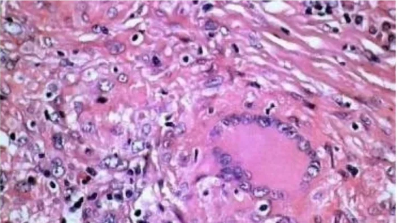

1.Masson三色染色法

用途及原理:称马松染色,经典的结缔组织染色法,用于鉴别胶原纤维和肌纤维。对肝硬化和肝炎导致的纤维增生、肾脏疾病诊断有重要价值。染色原理基于染料分子大小和组织渗透性。淡绿或苯胺蓝分子量大,染色后肌纤维红色,胶原纤维绿色或蓝色,便于区分。